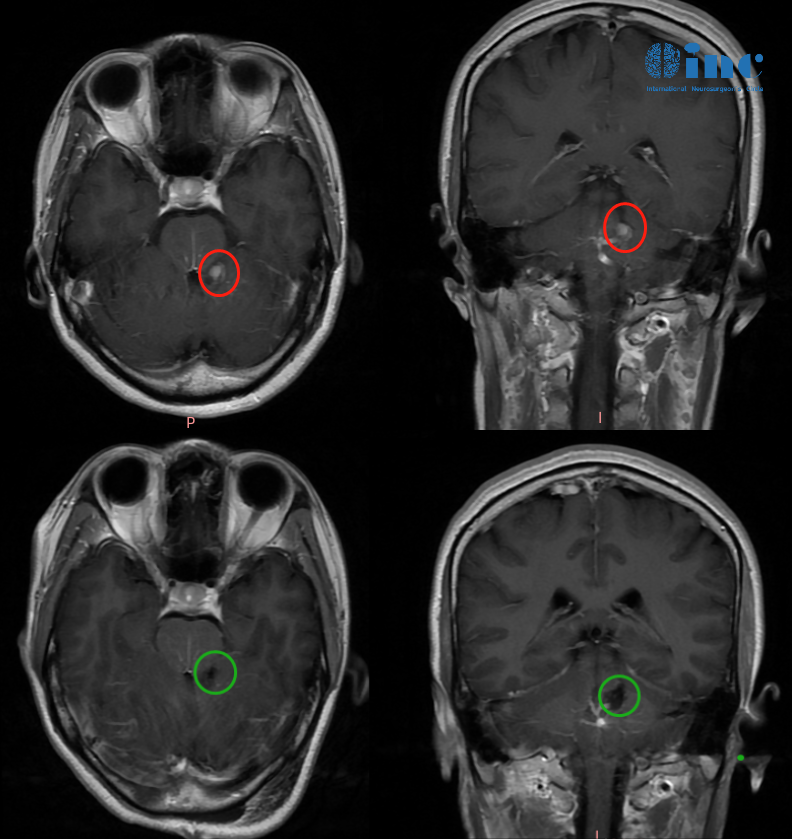

晓玲术前术后影像对比

鉴于病情进展,家人立即送晓玲至当地医院就诊。颅脑CT及MRI检查示:左侧桥脑及第四脑室高密度影,伴右侧小脑陈旧性出血灶。影像学诊断考虑为海绵状血管瘤合并静脉畸形。